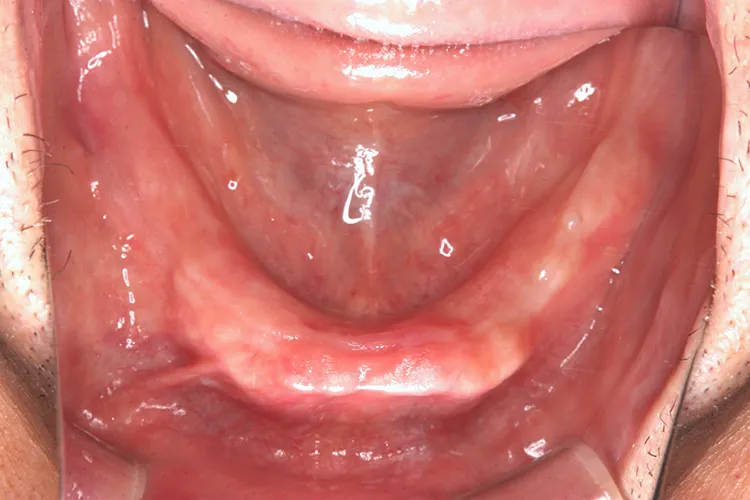

症例8/

下顎ボーンアンカードブリッジ

- 治療期間

- 6ヶ月

- 費用

- 265万円(税込)

治療前

治療後

レントゲン画像

治療内容

ボーンアンカードブリッジの下顎症例です。同じようにインプラント6本で上部構造を支えることができます。